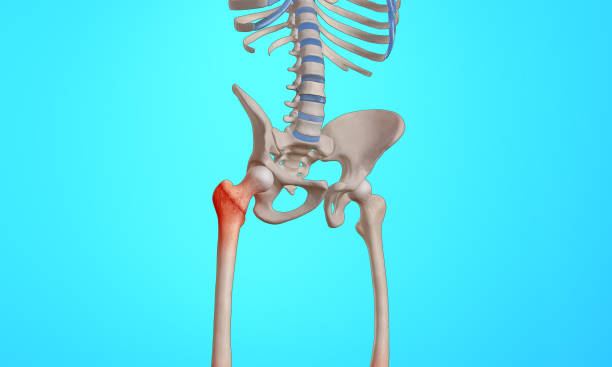

허리 통증과 햄스트링의 관계

허리 통증은 종종 햄스트링 문제와 관련이 있습니다. 요추 전만 자세를 따라하면서 통증이 더 심해지거나 악화되는 경우, 이는 햄스트링의 문제로 해석될 수 있습니다. 실제로, 이와 같은 증상을 겪는 분들 중 80% 이상이 햄스트링의 문제가 있다고 합니다.

척추의 모양은 S자형이며 요추의 중립 자세는 C자형입니다. 그러나 햄스트링이 단축되면 골반이 뒤로 넘어가게 되어 후방경사 상태가 되며, 이로 인해 요추 전만이 감소합니다. 햄스트링이 항상 단축되어 있는 상태에서 요추 전만 자세를 유지하려고 하면 척추 근육과 인대에 부하가 증가하고, 결과적으로 척추 관절의 불안정성과 통증의 원인이 될 수 있습니다.

햄스트링의 단축을 푸는 것이 요추 전만 자세를 유지하는 데 도움이 됩니다. 햄스트링 단축을 완화하기 위한 몇 가지 스트레칭 운동을 시도해 볼 수 있습니다. 또한, 허리 통증이 있는 경우, 햄스트링 문제와 관련된 가능성을 고려해 봐야 합니다.